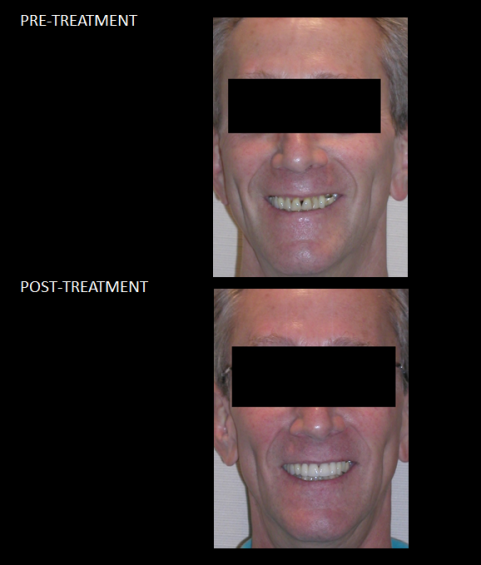

Full Mouth Reconstruction - restoring missing tooth structure (from years of tooth wear) using high strength crowns gave this man his smile back, improved his chewing, and helped protect his teeth from future damage.

Full Mouth Reconstruction - restoring missing tooth structure (from years of tooth wear) using high strength crowns gave this man his smile back, improved his chewing, and helped protect his teeth from future damage.

Full Mouth Reconstruction - restoring missing tooth structure (from years of tooth wear) using high strength crowns gave this man his smile back, improved his chewing, and helped protect his teeth from future damage.

Full Mouth Reconstruction - restoring missing tooth structure (from years of tooth wear) using high strength crowns gave this man his smile back, improved his chewing, and helped protect his teeth from future damage.